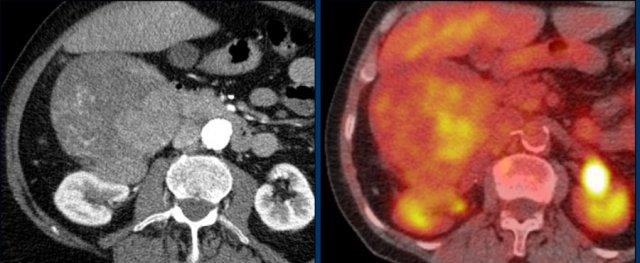

CT thì tĩnh mạch mặt cắt ngang này cho thấy một khối tuyến thượng thận phải kích thước rất lớn, nghi ngờ ác tính dựa trên kích thước lớn và tính không đồng nhất.

Tổn thương này là ung thư biểu mô vỏ thượng thận, nhưng trái với ví dụ trước, PET-CT FDG thực hiện tiếp theo cho mục đích phân giai đoạn chỉ cho thấy sự hấp thu nhẹ và chỉ ở phần ngấm thuốc mạnh nhất của khối u.

Hầu hết các ung thư biểu mô vỏ thượng thận đều có sự hấp thu FDG mạnh.

Sự thiếu hụt hấp thu FDG này có thể do khối u độ thấp với tốc độ phân bào thấp hơn hoặc có các thành phần xuất huyết hay hoại tử lớn.